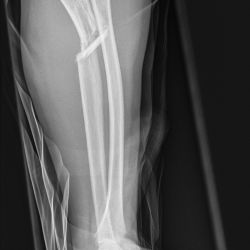

Monteggia-Fraktur